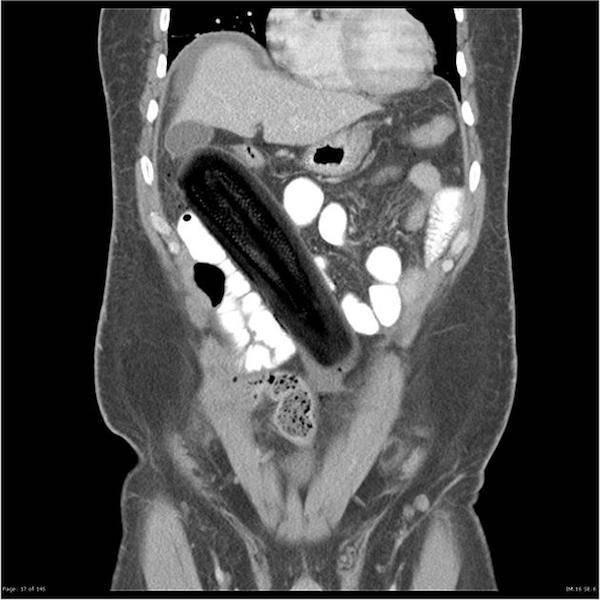

On suorastaan käsittämätöntä katsoa millaisia esineitä ihmiset nielevät ja tunkevat alapään kautta sisään. Röntgenosastolla työskentelevillä lääkäreillä on varmasti aika ajoin naurussa pidättelemistä, kun he löytävät alapäästä viinipulloja, kesäkurpitsoja ja jopa munakoisoja! Ihmiset ovat todella erikoisia varsinkin silloin, kun he yrittävät tyydyttää halunsa. Mukana on myös kuvia tapauksista, jotka sattuivat täysin vahingossa.#1 Naisen vatsasta löytyi 78 ruokailuvälinettä

#5 Kesäkurpitsa